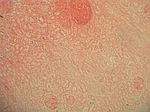

Nierenrindennekrose, HE